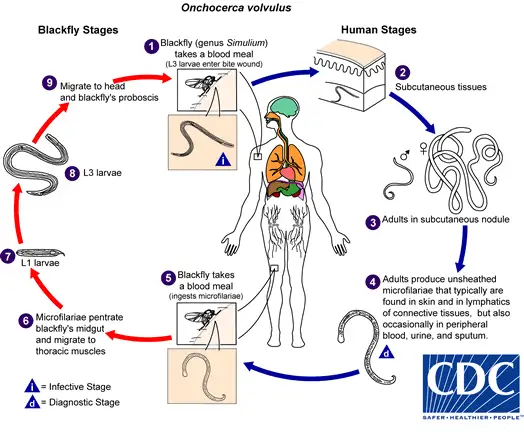

当雌性黑蝇叮咬已被感染的人类时,它会吸入含有微丝蚴的血液。这些微小的幼虫在黑蝇体内经历令人惊叹的蜕变。它们从蚊子的中肠穿越血腔,到达胸部肌肉,在那里经历两次蜕皮,最终发育成具有感染力的第三期幼虫。这个过程需要6至12天,期间黑蝇体内的温度和生化环境为幼虫提供着完美的培养皿。

成熟的感染性幼虫会向前迁移至黑蝇的头部和口器。当这只黑蝇再次叮咬人类时,幼虫便从口器中钻出,穿透人类的皮肤,开始它们在最终宿主体内长达十四年的寄生生涯。一只被感染的黑蝇可能携带数百条幼虫,而一次叮咬便足以完成传播。然而,黑蝇的传播效率其实相当低下——与传播疟疾的按蚊相比,需要数百次叮咬才能完成一次成功的传播。这解释了为什么河盲症主要影响长期生活在流行区的居民,而旅行者鲜少感染。

盘尾丝虫是地球上最成功的寄生虫之一。它的成虫形态可以在人体内存活长达14至15年,这是绝大多数寄生虫望尘莫及的寿命。更惊人的是,雌性成虫在其一生中可以产下数以百万计的微丝蚴,平均每天释放约1000至3000条幼虫。

当感染性幼虫进入人体皮肤后,它们会在数月内发育成熟。雄虫相对较小,体长约2至4厘米,细如发丝;而雌虫则可达30至50厘米长,直径约0.3至0.4毫米,是名副其实的"巨虫"。成虫并不四处游荡,它们将自己蜷曲成团,深埋在皮下结缔组织中,形成特征性的纤维结节——医学上称为"盘尾丝虫结节"或"蟠尾蚴瘤"。

然而,真正造成伤害的不是成虫,而是它们生产的微丝蚴。这些微小的幼虫体长仅约300微米,直径不到1微米,必须在显微镜下才能观察到。它们没有围鞘,身体纤细,尾部逐渐变尖。一旦离开母体,微丝蚴便开始在宿主的皮肤和皮下组织中四处迁移。

微丝蚴的迁移模式堪称生物学奇观。它们似乎具有某种趋性,会主动向皮肤表面移动。研究表明,微丝蚴在皮肤中的分布并非随机——在躯干部位密度最高,而在四肢末端相对稀少。这种分布模式可能与黑蝇的叮咬偏好有关,也可能是寄生虫为确保传播而进化出的策略。